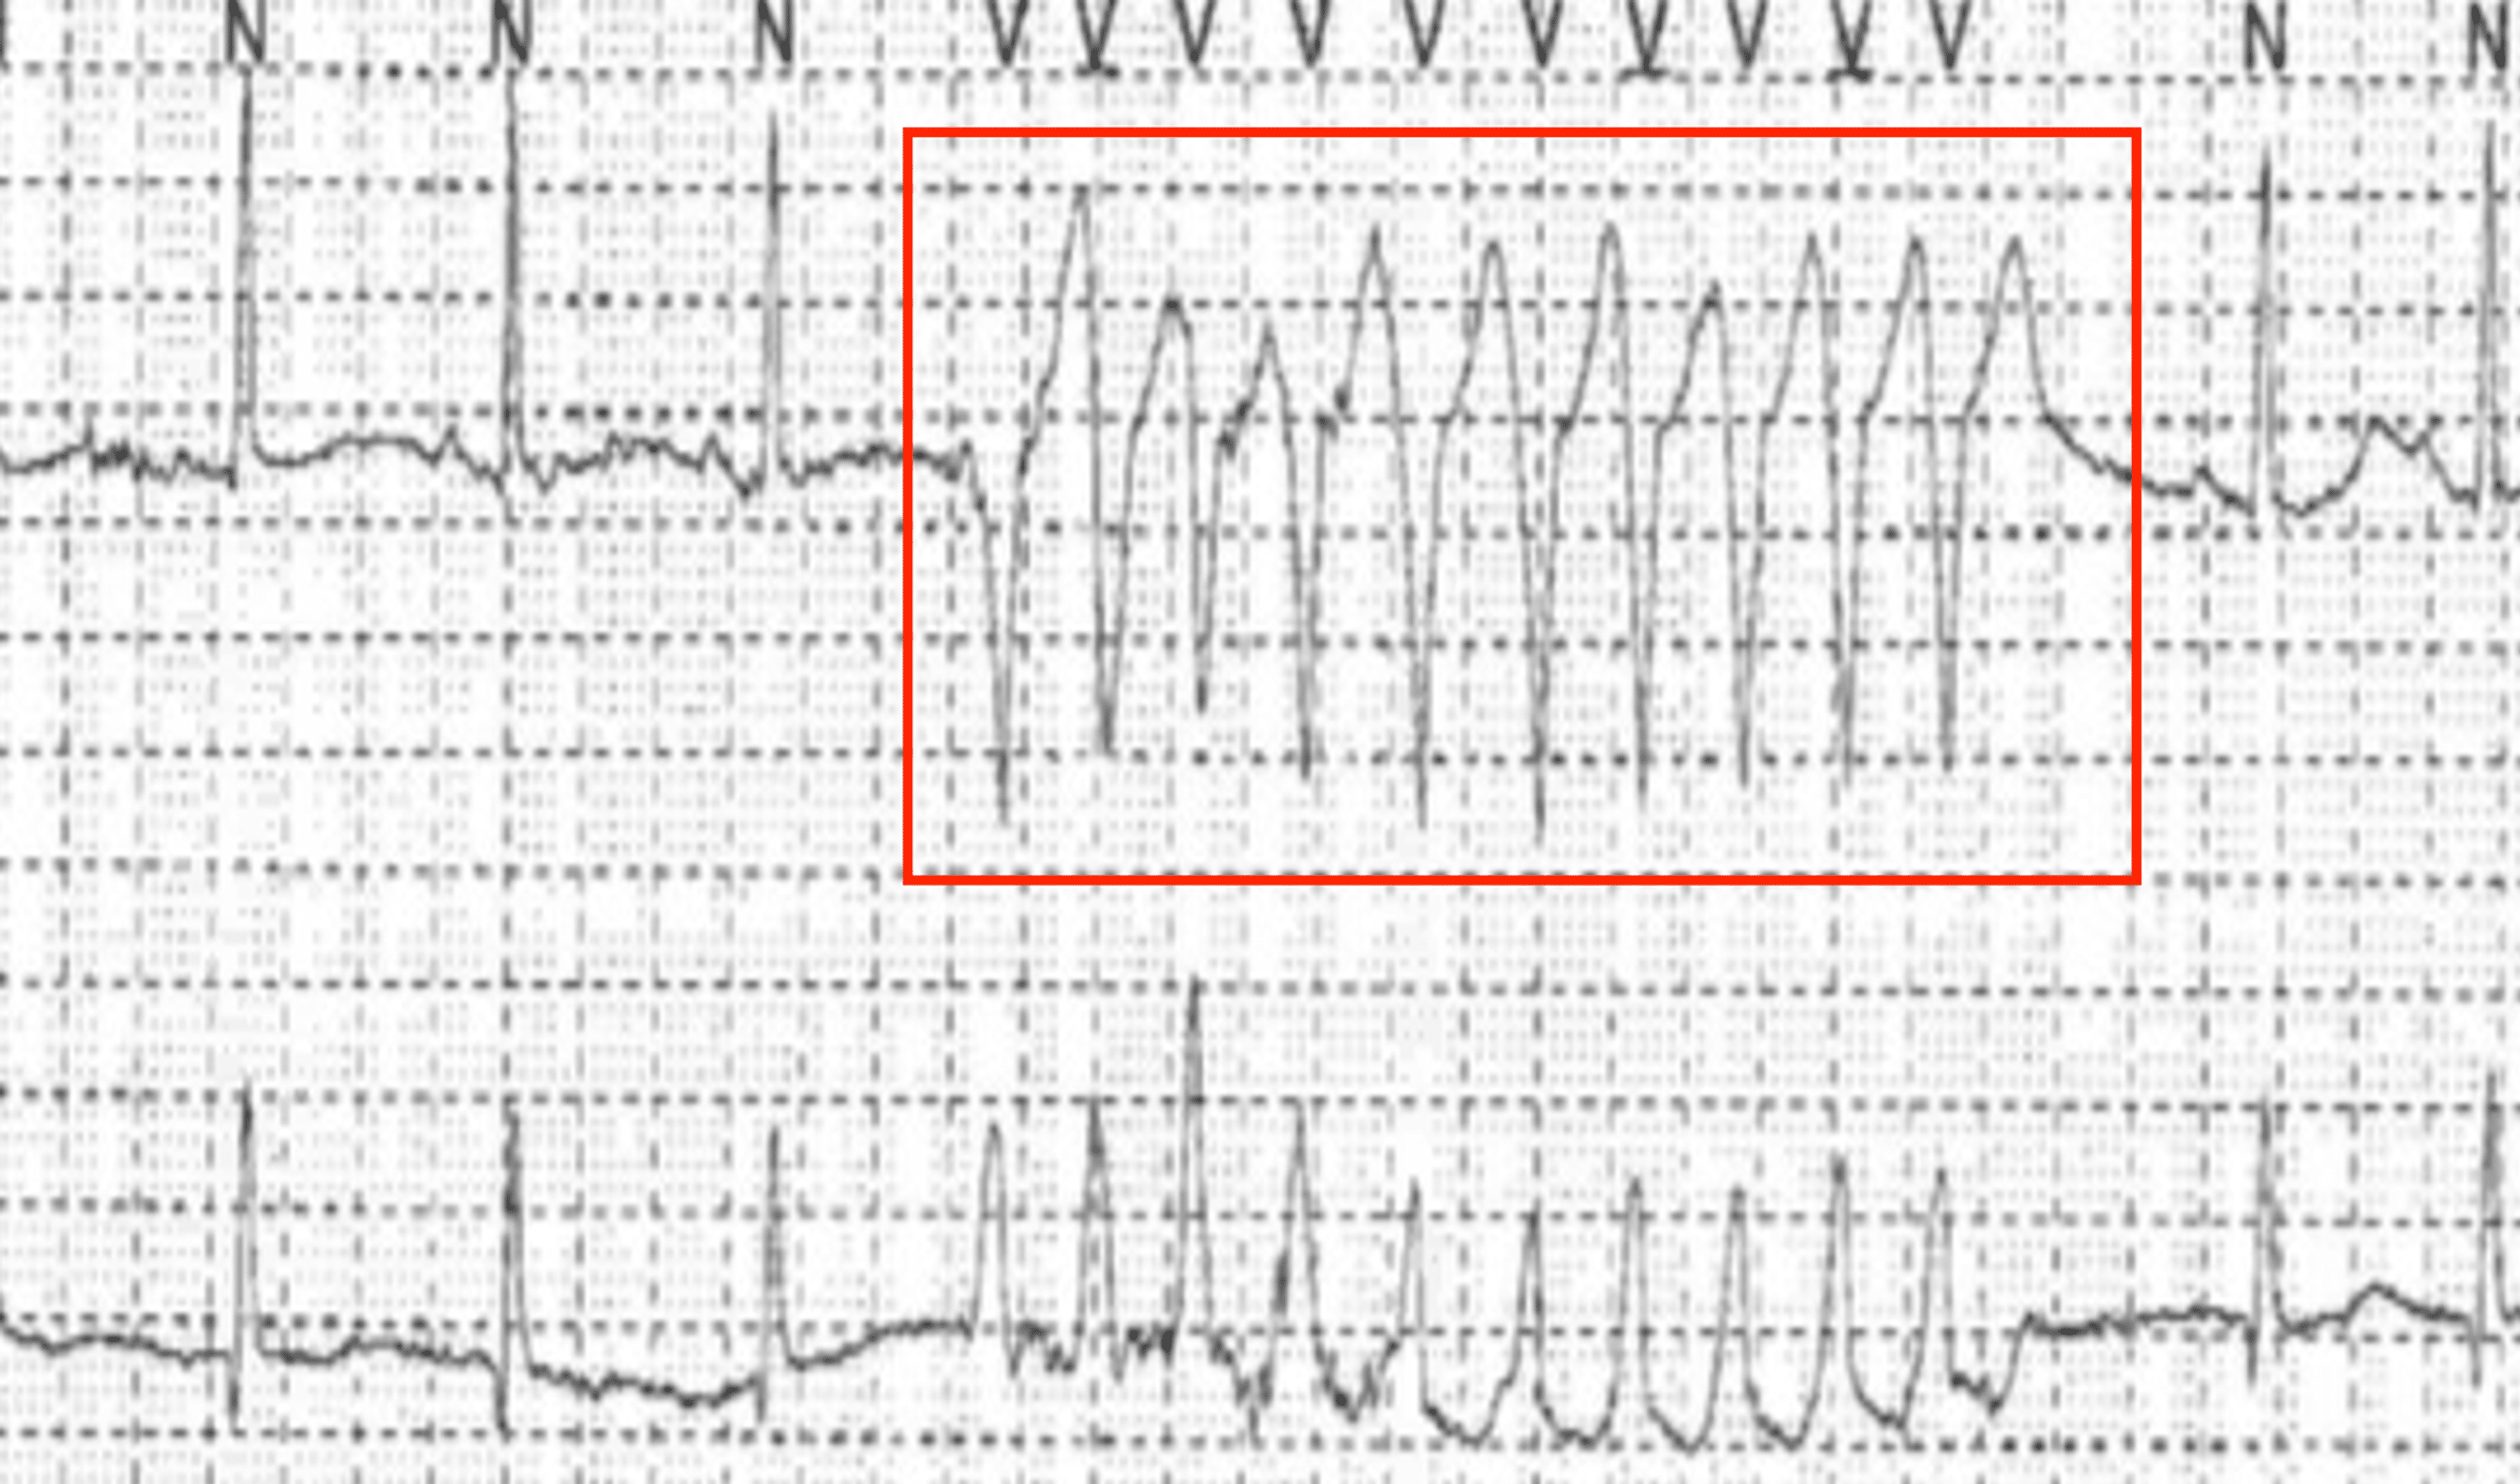

(A) . Holter monitoring sustained 166 regular heartbeats per minute Pvc In Holter Monitor Holter monitor studies suggest that up to 75% of people experience pvcs without any symptoms. It is also imperative to quantify the. In patients with a high burden of pvcs (>10%), electrocardiography, holter monitoring, and echocardiography are critical in assessment of pvc characteristics that help guide. If you don't have premature ventricular contractions (pvcs) very often, a standard may not. Pvc In Holter Monitor.

Holter monitoring showing premature ventricular contractions (PVCs) in Pvc In Holter Monitor It is also imperative to quantify the. Holter monitor studies suggest that up to 75% of people experience pvcs without any symptoms. But if they cause significant symptoms, like feeling faint, talk with your doctor. If you don't have premature ventricular contractions (pvcs) very often, a standard may not detect them. In patients with a high burden of pvcs (>10%),. Pvc In Holter Monitor.